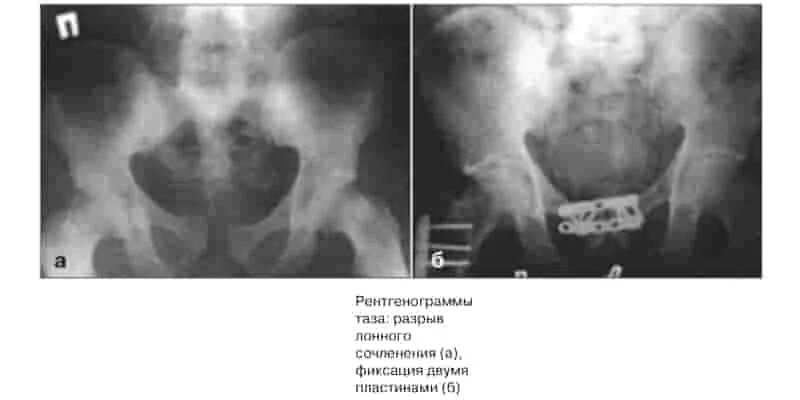

Код по мкб 10 перелом костей таза